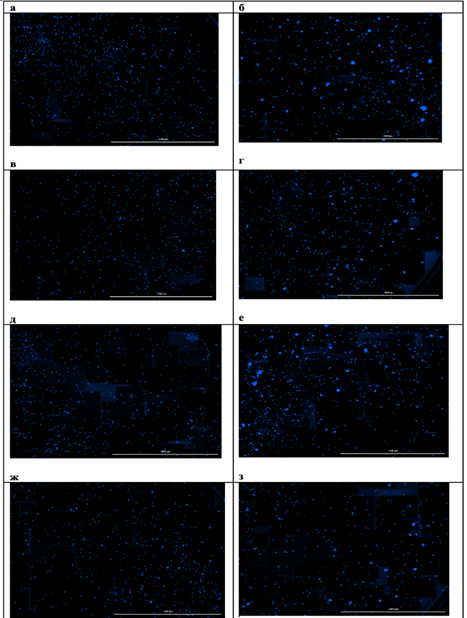

При исследовании чувствительности мононуклеарных клеток периферической крови к берберинуin vitroбыло выявлено стимулирующее влияние берберина на их пролиферативную способность, проявлявшееся увеличением количества и площади формируемых колоний. При этом благоприятный клинический исход ассоциировался не с более высокой базальной колониеобразующей активностью, а с формированием более крупных колоний, что может отражать наличие лимфоцитарных клонов с более высоким пролиферативным и метаболическим потенциалом. Это позволяет предположить, что прогностическое значение может иметь не общее число клеток, а качественные характеристики клонального пролиферативного ответа (рис.3, 4).

Рис.3. Микрофотографии образовавшихся колоний мононуклеарных клеток периферической крови пациента с благоприятным исходом: а – контрольная проба, б – контрольная проба с добавлением ФГА, в – проба с добавлением 1мкмоль/л берберина, г – проба с добавлением 1мкмоль/л берберина и ФГА, д – проба с добавлением 2мкмоль/л берберина, е – проба с добавлением 2мкмоль/л берберина и ФГА, ж – проба с добавлением 4мкмоль/л берберина, з – проба с добавлением 4мкмоль/л берберина и ФГА.

Примечание: составлен авторами по результатам данного исследования

Рис.4. Микрофотографии образовавшихся колоний мононуклеарных клеток периферической крови пациента с неблагоприятным исходом: а – контрольная проба, б – контрольная проба с добавлением ФГА, в – проба с добавлением 1мкмоль/л берберина, г – проба с добавлением 1мкмоль/л берберина и ФГА, д – проба с добавлением 2мкмоль/л берберина, е – проба с добавлением 2мкмоль/л берберина и ФГА, ж – проба с добавлением 4мкмоль/л берберина, з – проба с добавлением 4мкмоль/л берберина и ФГА.

Примечание: составлен авторами по результатам данного исследования

У пациента с благоприятным клиническим ответом изначально отмечалась более низкая базальная колониеобразующая активность МНПК: количество колоний было на 56% меньше по сравнению с пациентом с рефрактерным течением заболевания, однако их средняя площадь превышала данный показатель на 22%. Воздействие берберина в исследованных концентрациях вызывало дозозависимое усиление колониеобразующей способности МНПК у обоих пациентов, при этом наибольшая стимуляция наблюдалась при сочетанном применении берберина и фитогемагглютинина, что свидетельствует о синергическом эффекте изучаемого соединения с митогенной стимуляцией (рис.5, 6). Использование ФГА позволило оценить влияние берберина в условиях активированной иммунной реакции, что приближаетмодель in vitro к условиям реализации противоопухолевого иммунного ответаin vivo.

Кроме того, были выявлены индивидуальные различия в чувствительности МНПК к берберину: у пациента с полным ответом на терапию наибольшее увеличение количества колоний наблюдалось при концентрации 1мкмоль/л, тогда как у пациента с неблагоприятным исходом пик пролиферативного ответа смещался на 2мкмоль/л (рис.5). Полученные различия могут объясняться особенностями метаболической и пролиферативной активности отдельных лимфоцитарных клонов. Более крупные колонии у пациента с благоприятным исходом могут отражать наличие клонов с высоким метаболическим потенциалом и способностью к интенсивному клеточному делению, тогда как большее число, но мелких колоний у пациента с неблагоприятным исходом может соответствовать функционально менее активным клональным линиям.